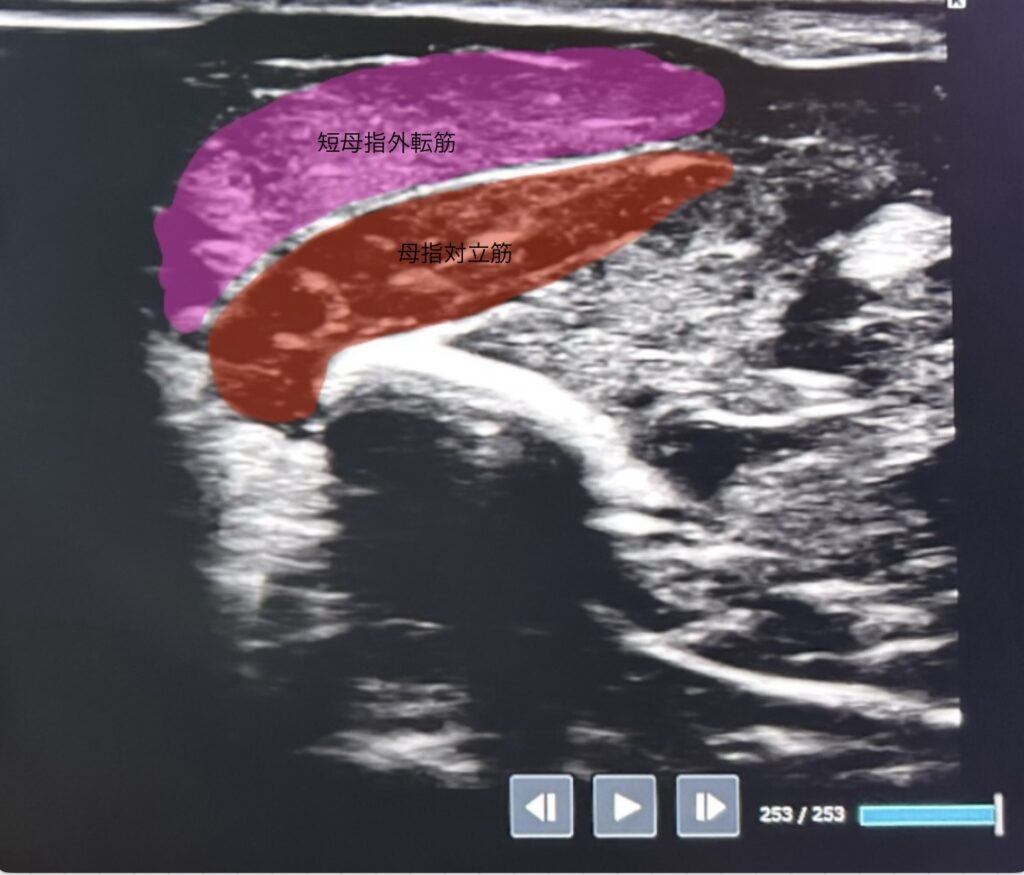

①母指外側

短母指外転筋:母指の外転

母指対立筋:母指の対立(小指とくっつける)